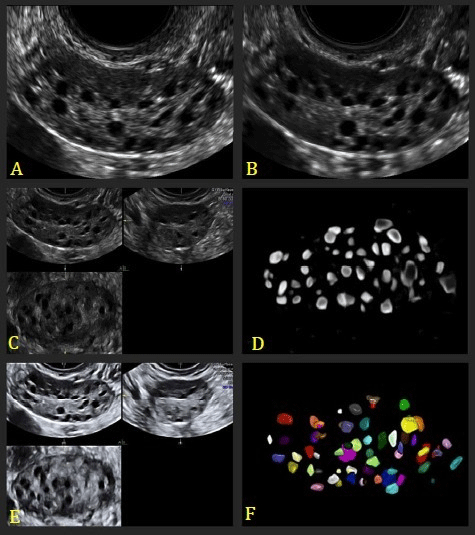

1、2D阴超检查

在2D阴超检查的时候必须进行进行对膀胱排空后方可进行,而常常需要在两个平面进行连续的扫查,找出成像较佳平面,并进行超声调整后再做最为准确的卵泡液与卵巢间质间的对比度。

2D阴超优点与缺点

• 1优点在于利用谐波的帮助来减少伪影并改善图片的质量,让其更加具有对比度;

• 2缺点在于因为再检查的时候受到衰减的影响较大,距离越远那么成像效果就越差。

2、3D阴超检查

相对于2D阴超来说3D阴超下过要好一点,3D阴超是同时利用3个垂直平面存储和分析产生体积,通过多平面交叉进行窦卵泡计数检查,将效果发挥到最佳,在较好切面直接进行最佳图像参数和最大采集角,将成像图片质量提升到最高

3D阴超优点与缺点

• 1优点常来说在于采集的熟读更加的快,有着明显减少阴超扫查的时间;

• 2在3D阴超来说任然是有一定局限性的,即便在计数后也需要进行手动修正。